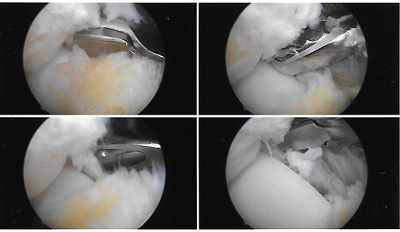

Mit kleinsten Instrumenten entfernt Dr. Cserhati, was in meinem Sprunggelenk Ärger macht, z. B. das sogenannte Bassett-Ligament.

Der Eingriff erfolgt athroskopisch, also nur mit zwei kleinen Schnitten und einer Kamera im Sprunggelenk. So kann ich auf einem Bildschirm zuschauen, was in meinem Fuss passiert. Cool! Dr. Cserhati erklärt mir alles, was ich dort sehe und was er macht. Wie er bei den Voruntersuchungen vermutet hat, sind beim Verheilen meiner Bänderzerrungen verdickte Vernarbungen entstanden, die für den Dauerschmerz gesorgt haben. Er zeigt mir diese und «putzt» sie mit einem klitzekleinen Instrument weg. Dann geht der Kamerablick weiter zum sogenannten «Bassett-Ligament», ein kleines diagonales Band im Sprunggelenk. Man kann dieses mit dem Blinddarm vergleichen: Man braucht es nicht wirklich, aber es kann Probleme machen, nämlich indem es einklemmt. Also weg damit. Mit einem Instrument, das aussieht wie ein Krokodil, wird der Störenfried «weggefressen». «Diese Krokodilschnauze ist nur 2 mm breit», erklärt mir Herr Cserhati die Dimensionen auf dem Bildschirm. Unglaublich, dass etwas so Kleines solchen Ärger machen kann.